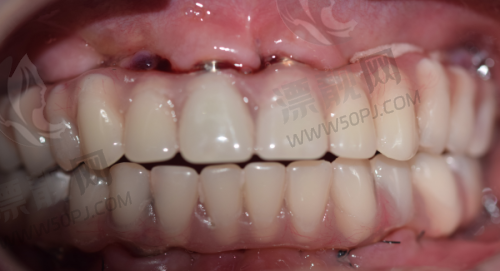

强项:高难度种植、全口修复、吸附性义齿

鼎植口腔在本地做种植牙的人中几乎是“必打卡单位”,医生高振华和黎强在种植牙领域经验颇为丰富,擅长全口吸附性义齿、即刻种植等复杂病例处理。此外,术前会有CBCT影像分析和3D导板定位,精细度特别高。价格一般,活动期间国产种植体可低至2980元/颗。